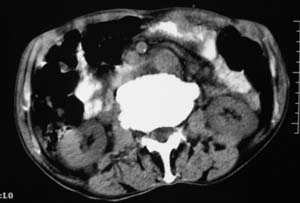

右侧肾上腺区可见软组织密度肿块,密度欠均匀,未见钙化;右肾下极内侧可见实质局限性增厚并呈肿块样突出肾轮廓.

右侧心膈多角处还有一个类圆形结节哦

右侧肾上腺区软组织肿块影,密度不均,其周围及腹主动脉周围,心包周围均见多个淋巴结肿大.结合临床首先考虑:右肾上腺恶性肿瘤伴腹腔内及心包淋巴结转移.